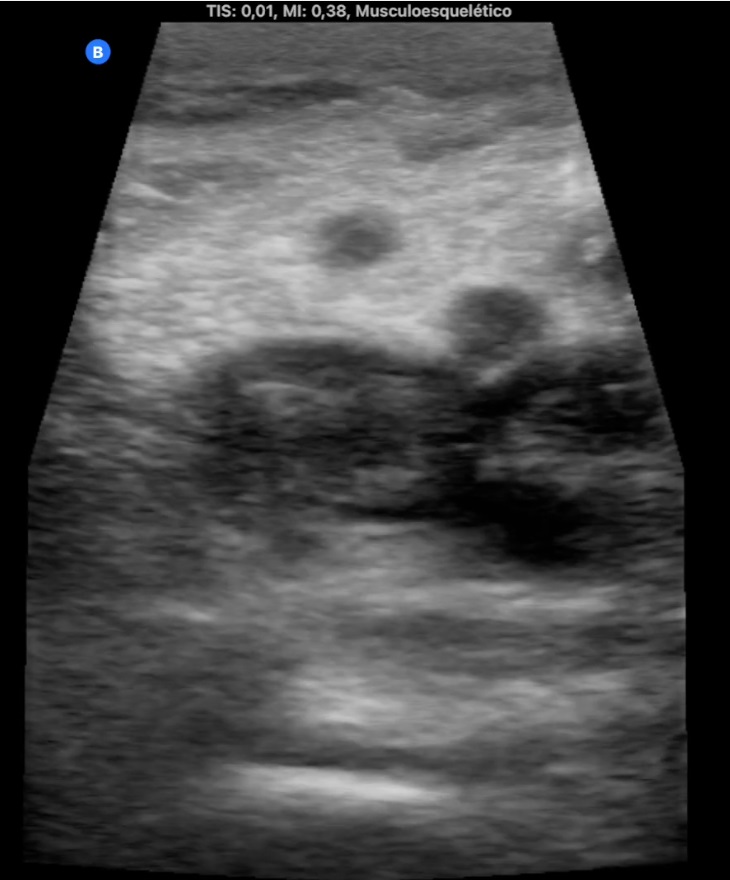

Hombre de 68 años con antecedentes de hernia de hiato/gastritis/úlcera duodenal, ex fumador desde hace 9 años y colelitiasis. Acude por edema y empastamiento de MID de 4 días de evolución (Imagen 1). Pérdida de peso de 5 kg en 2 meses. Analítica 20 días antes antes con Hb 14, LDL 150 y GGT 59, resto normal.

Descripción de los hallazgos ecográficos y las imágenes más relevantes para la resolución del caso

Ocupación de espacio con trombo venoso ecogénico desde poplítea hasta tercio superior, así como safenas externa e interna (imagen 2 femoral profunda e imagen 3 safena mayor). Lesión isoecogénica en segmentos hepáticos V/VI de 6,65 x 5,87 cm (imagen 4).